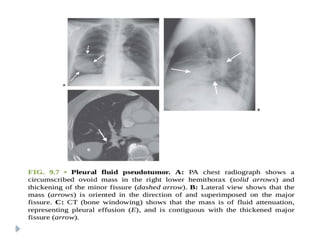

PLEURAL PSEUDOTUMOR

⚫ Is a fluid collection within the lung fissure.

⚫ Most common site : MINOR FISSURE

⚫ Common causes include :

 Congestive heart failure

 Cirrhosis

 Renal insufficiency

⚫ On chest radiographs:

⚫ Classical lenticular or biconvex opacity is seen in

the fissure.

⚫ Usually resolves after therapy with diuretic

agents